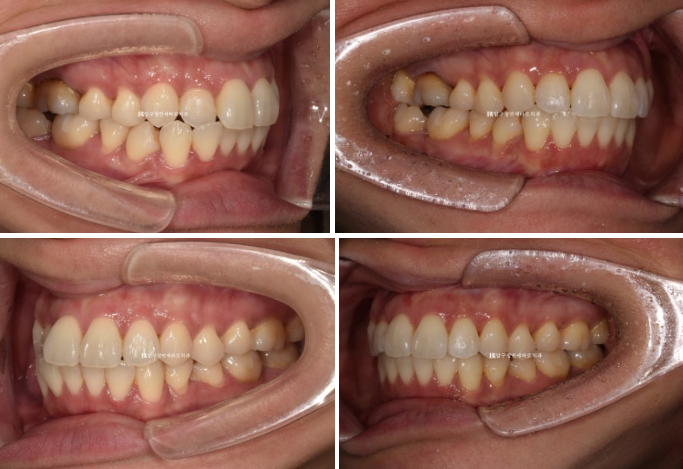

Left - Before treatment / Right - After treatment

23.10~24.01

The originally good occlusion was well maintained.

Bite blocks attached to the molars are often used in full orthodontic treatment, but if used for too long, the teeth in that area can become intruded into the bone, causing the bite to open as a side effect.

Because this was short-term partial orthodontic treatment for the front teeth, the bite blocks were used for only 3 months, and after removal, the occlusion in this area remained well maintained.